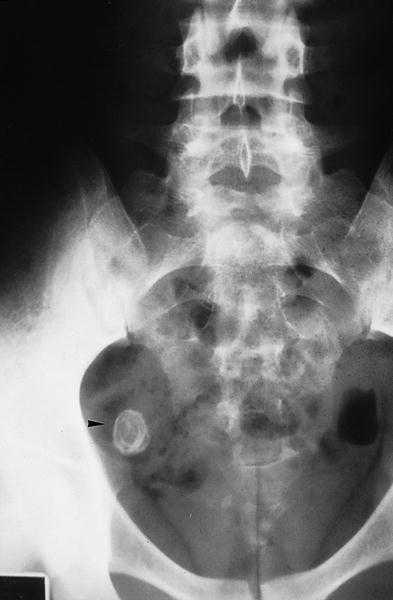

Se solicitó de urgencias, una radiografía simple de abdomen (fig. 1) en la que se observó una imagen densidad calcio, en capas concéntricas, proyectada sobre fosa ilíaca derecha, compatible con apendicolito, tras la cual se decidió solicitar una ecografía abdominal y de fosa ilíaca derecha (fig. 2), en la que se evidenció la existencia de un asa fija, aperistáltica, con su base en el ciego, que terminaba en dedo de guante, dolorosa a la presión y que media más de 6 mm, con una distribución en capas de ecogenicidad alternante y con imagen cálcica en su extremo distal, hallazgo que posteriormente se confirmó con la tomografía computarizada (TC) abdominopélvico (fig. 3). Por todo ello se realizó el diagnóstico de apendicitis aguda catarral-flemonosa, con apendicolito distal.

Fig. 3.